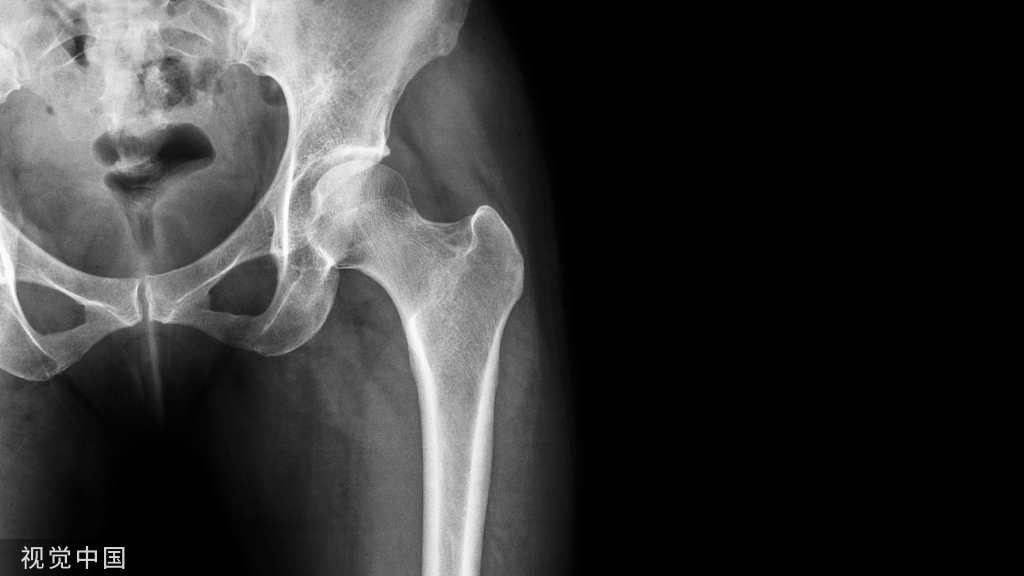

(4)术后7d复诊,患者左侧面颊无明显肿胀,张口度约4指,局部伤口愈合良好,36无松动,叩诊(-),牙髓活力正常,左侧下唇痛觉、触觉与右侧无明显差异。影像学检查示37、38拔除术后局部无异常(图4a-4b)。

4a:术后7d曲面断层影像;4b:术后7d术区情况;4c:术后1月术区情况